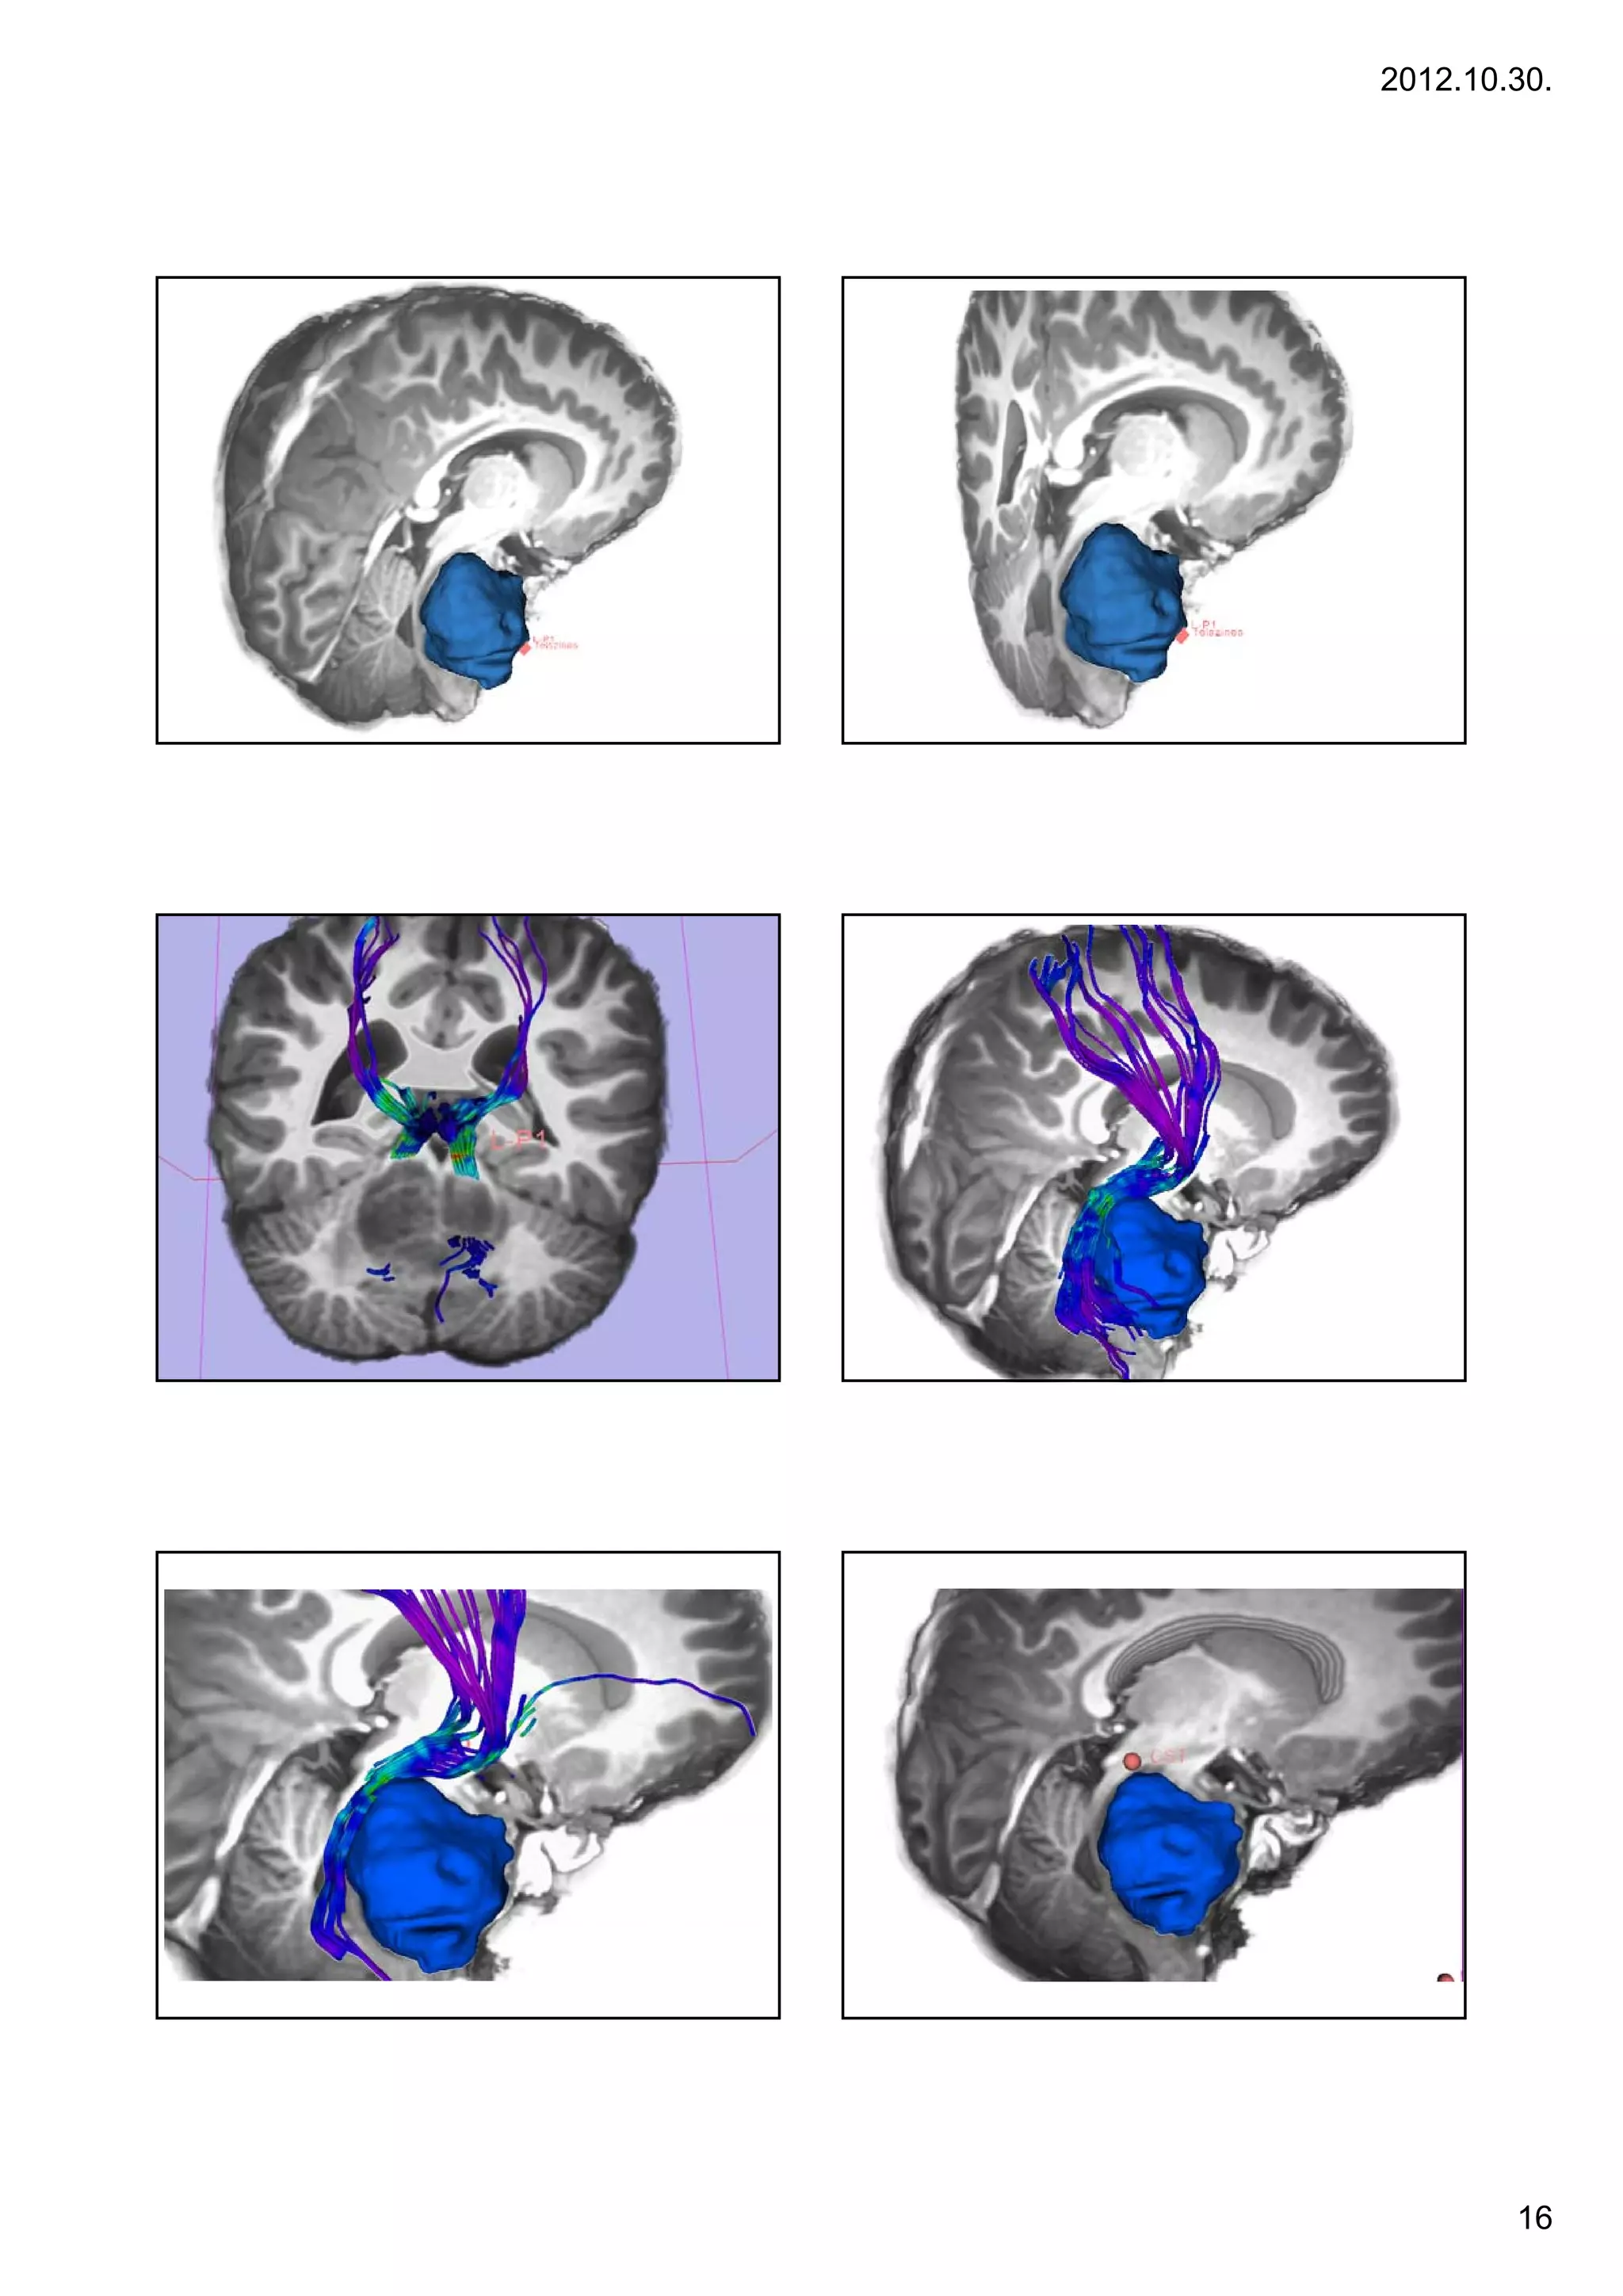

arise from the midbrain or medulla.                                                3 yr, F, ICP signs, cerebellum – tonsillar herniation

Jobb oldali nézet

Elülső nézet                felülnézet

jobb                                    Bal

sin

jug   ICA

Hátsó nézet a IV.

agykamra felől